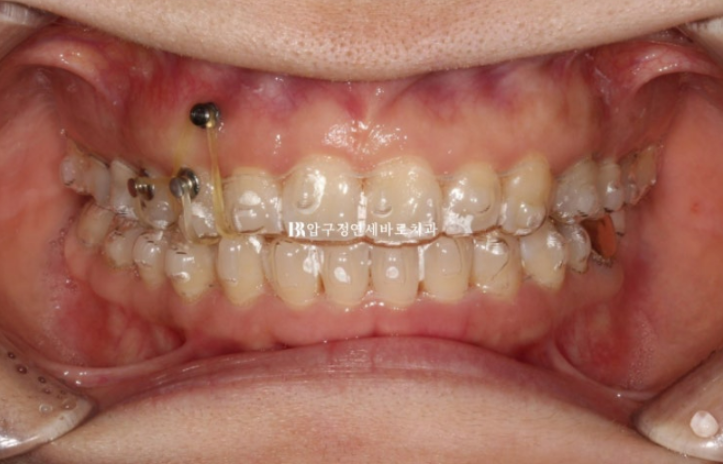

전 후 비교 보겠습니다.

치료기간은 총 11개월이고 재제작은 1회 했습니다.

24.01~24.12

11개월이라는 길지 않은 시간에 교합평면과 치축이 완전히 개선이 되었습니다.

앞으로 재발방지를 위해 유지장치 디자인, 종류가 특별히 고려되어야 합니다.

과개교합이 있을 당시 윗니에 가려 숨어있던 아래 앞니 때문에 쏙 들어가있던 아랫입술도 교정 후 볼륨감을 회복하였습니다.

한쪽 치열을 올려내어 교합평면을 바로잡는 캔팅 교정은 인비절라인으로 잘 되는 교정 중 하나입니다.